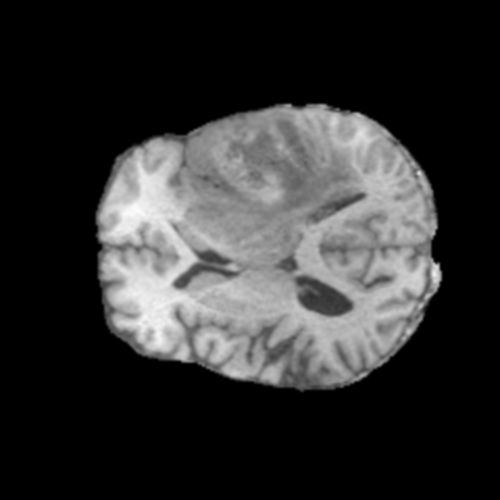

Ejemplos de Modalidades MRI

Visualización de las 4 modalidades de resonancia magnética y las segmentaciones de zonas tumorales utilizadas para entrenar el modelo

Glioma de Bajo Grado (LGG)

FLAIR LGG

FLAIR

T1ce LGG

T1ce

T2 LGG

T2

T1 LGG

T1

Núcleo LGG

Núcleo

Edema LGG

Edema

Realce LGG

Realce

Tumor Completo LGG

Tumor Completo

Núcleo Edema Realce